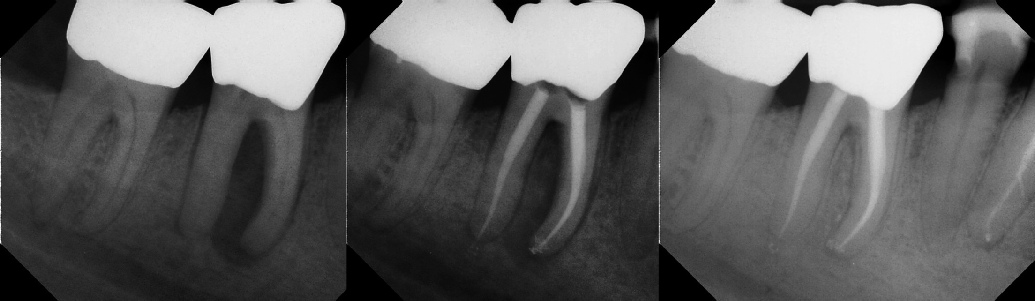

COMPLICATED ANATOMY LARGE LESIONS CALCIFIED CANALS PERFORATION / RESORPTION SEPARATED INSTRUMENTS SURGICAL CASES RETREATMENT / pOST REMOVAL OPEN APICES ACCESS THRU CROWNS Root Canal Case Portfolio

Pre-op Post-op 6 mos.